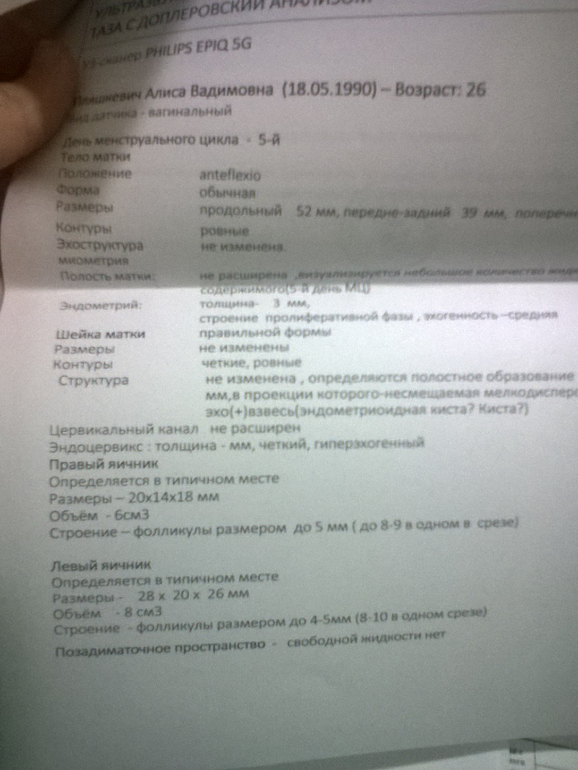

Девочки ,была на узи.Может кто поможет в расшифровке?)

Эндометрий 3 мм на 5 день цикла это нормально для планирования беременности или нет?

Нашли кисту на шейке матки.Влияет ли это на беременность ?

Яичники это не сильно большие ,а то в 5 мес назад они были в 2 раза меньше??

Нормальные показатели для вашего ДЦ.

Киста на ШМ точно не опасна. Я с ней забеременела, родила (сама без проблем) и сейчас она не мешает :)

Норм УЗИ. Толщина эндометрия для 5 дня цикла нормально. У вас только М. закончилась, новый еще не нарос ). На кисту забить. Гормональное. Как появилась, так может и кануть в лету. Такие вещи беременеть не мешают. Отверстие же в шейке не закрывает. Яичники как яичники. Что еще сказать. Если планируете не шибко долго, то насчет гормонов не заморачивайтесь. Если очень хочется, то лучше фоликулометрию сделайте в несколько циклов, посмотрите, есть О. или нет.